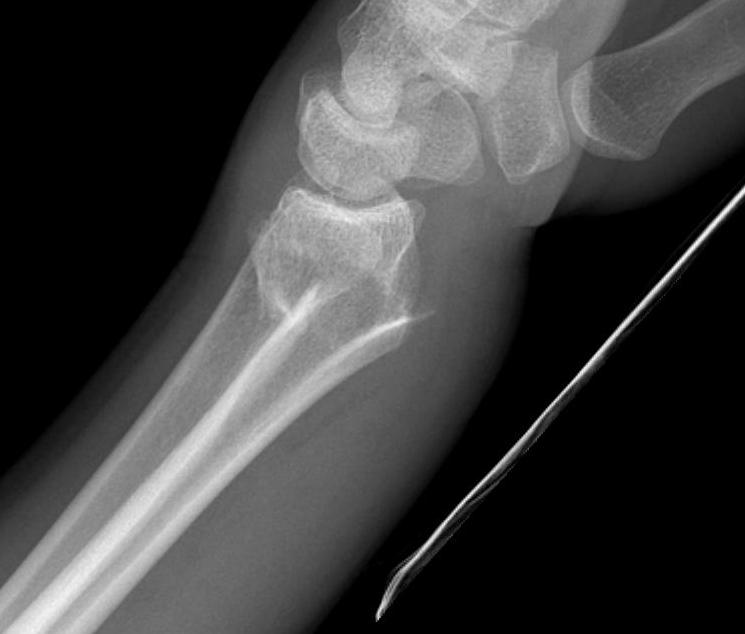

Distal Radius Fracture DRUJ incongruentDRUJ FractureDRUJ Fracture CT

Sigmoid notch disruption and DRUJ instability